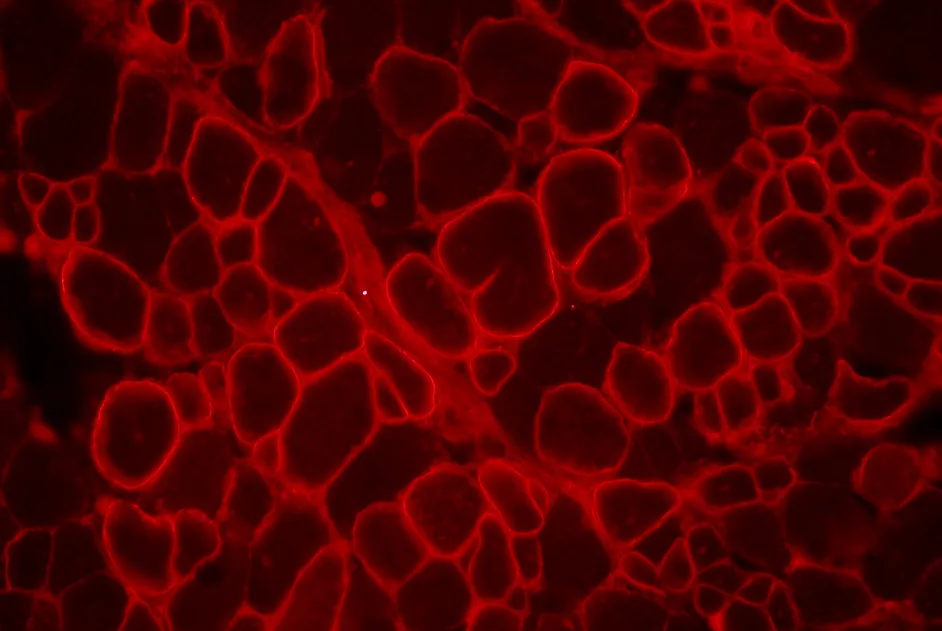

Une stratégie de double thérapie génique apportant les gènes de micro-dystrophine et de la follistatine restaure la force de souris mdx âgées.